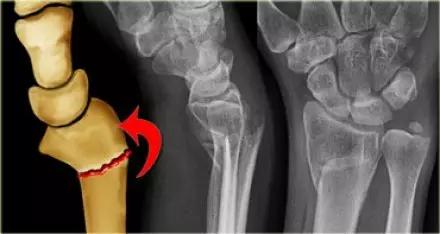

2. Colles 骨折

桡骨远端骨折,伴有桡骨远端向背侧的移位,可以有或没有尺骨干的骨折。具有这几个特征:背侧粉碎、向背侧成角、向背侧移位且挠骨短缩的关节外骨折。

典型 colles 骨折,枪刺样、餐叉样畸形

3. Smith 骨折

桡骨远端骨折伴骨折远端向掌侧移位,也称为反 Colles 骨折。